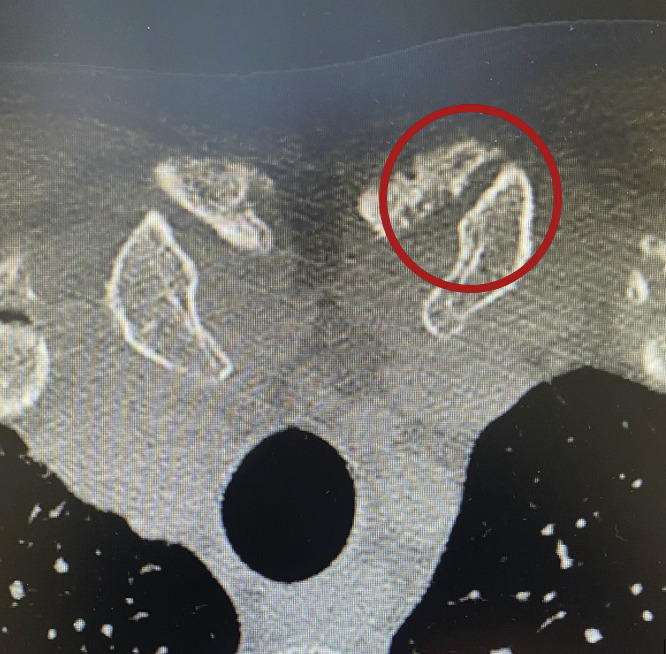

Concernant les examens complémentaires, la radiographie standard est d’interprétation difficile mais permet de ne pas méconnaître une fracture associée. L’examen de réfé­rence est le scanner (fig. 2) qui, par la reconstruction en trois dimensions, confirme la luxation ou la subluxation. Il permet par ailleurs d’analyser d’éventuels conflits avec les éléments médiastinaux en cas de disjonction postérieure.

Figure 2.